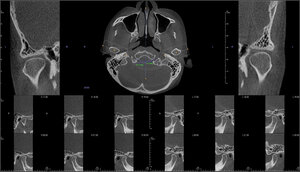

The patient’s CBCT (Figure 5) depicted in all slices, completely contiguous condyles that were fully corticated, normal skull base structures, and definitive disc space medial, posterior, and superior to both condyles. Her vertical mouth opening = 45 mm, indicating the visible TM Joint anatomy had a normal Range of Motion.